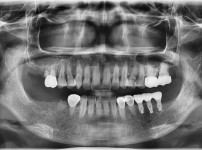

2

BEFORE

AFTER

클릭 해주세요.

임플란트 재식립 사례

임플란트